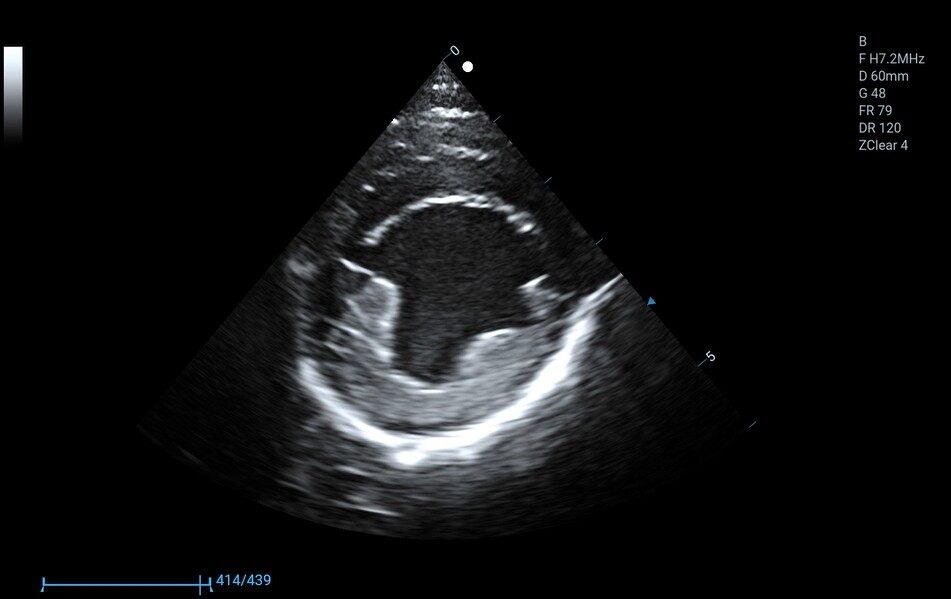

8P2MA ● 3.5-15.0MHz ● Single crystal phased array probe ● For Cardiology of felines |

3P2PA ● 1.0-6.5MHz ● Phased array probe ● For Cardiology of big-sized canines |

5P1PA ● 2.5-13.0MHz ● Phased array probe ● For Cardiology of small and medium-sized canines |

6C1PD ● 3.5-12.0MHz ● Micro convex array probe ● For Abdomen, Cardiology, Reproduction |